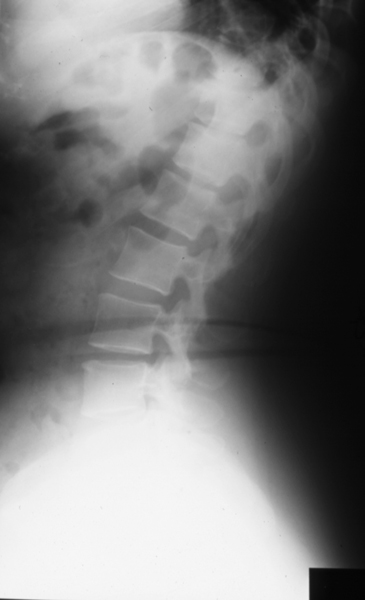

Radiology MS 185 - Normal Lumbar Spine

Identify: Lateral - vertebral body, disc space, neural foramen